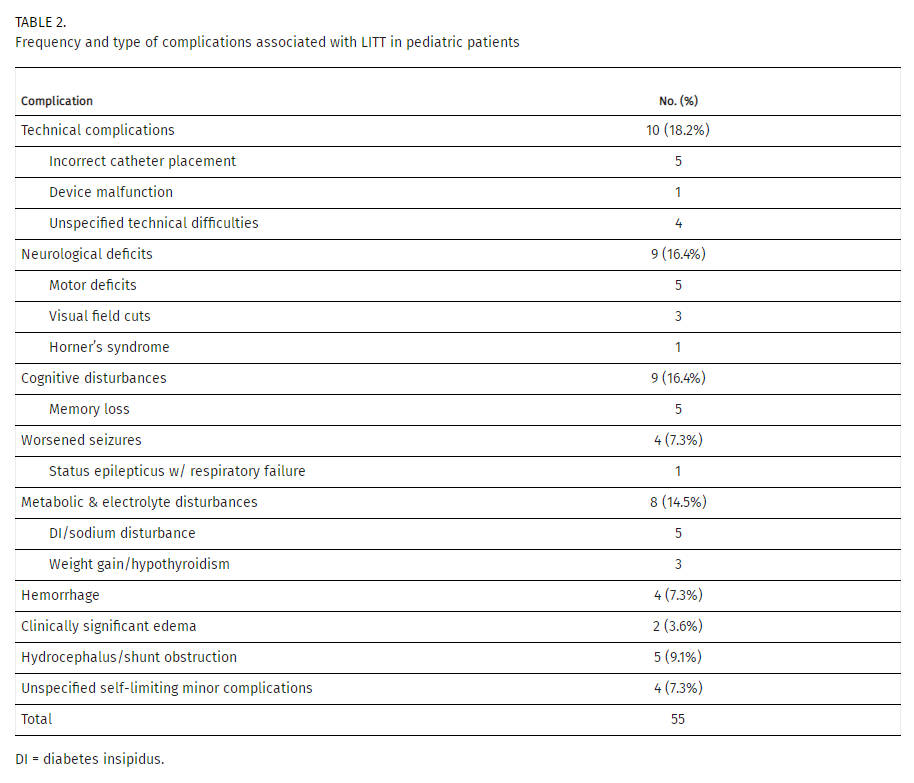

再按照手术方案设定手术入路轨迹后,插入激光探针准备消融

Rutka教授和他的团队正在为其手术